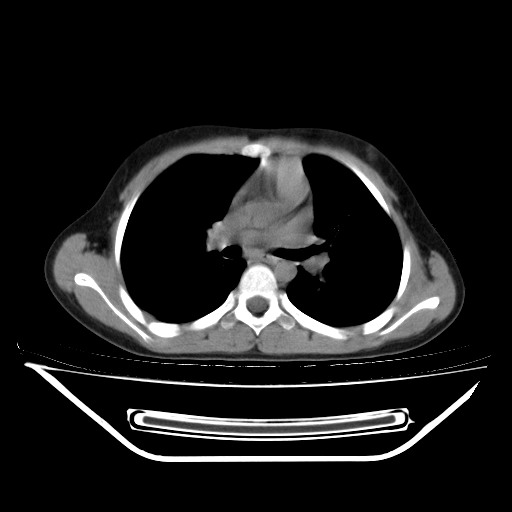

经过胸部穿刺活检为支原体感染。以下示抗支原体感染30天后所见,病灶明显缩小,临床症状消失: